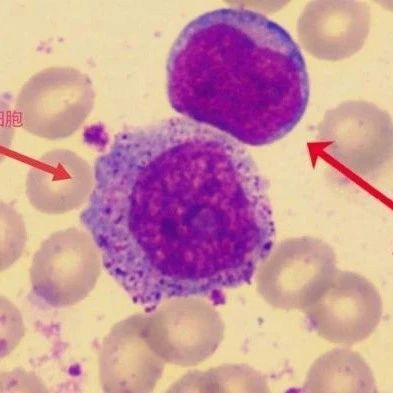

按ITP治疗七年未果,形态学助力罕见病诊断

2025-07-04 -

看图识细胞,提升形态学基本功 | 形态学周考